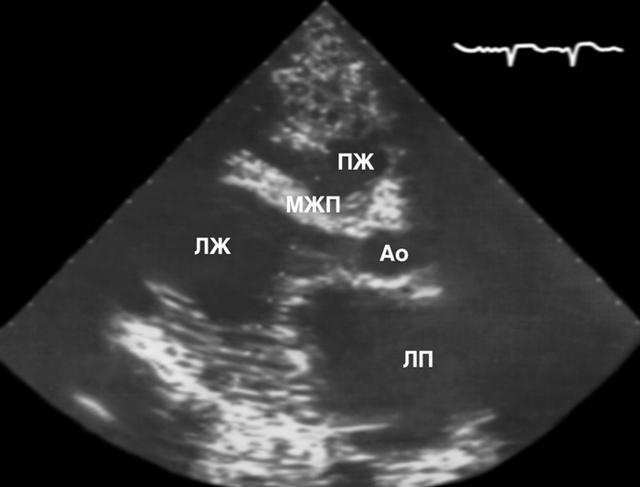

Рис. 3а). Двухмерная эхокардиограмма больного дилатационной кардиомиопатией: ПЖ — правый желудочек, Ао — аорта, МЖП — межжелудочковая перегородка, ЛЖ — левый желудочек, ЛП — левое предсердие, МК — митральный клапан, АК — аортальный клапан; пунктир — масштаб длины: расстояние между точками 1 см. Расширены все полости сердца (размеры ПЖ — 4,8 см, ЛЖ — 6,1 см, ЛП — 6 см); толщина МЖП менее 1 см, имеются признаки ее дискинезии; расстояние z между передней створкой митрального клапана и МЖП увеличено до 2 см (митрально-септальная сепарация); отмечается симптом малого выброса: сближение створок аортального клапана в систолу от расстояния Х до расстояния Y.